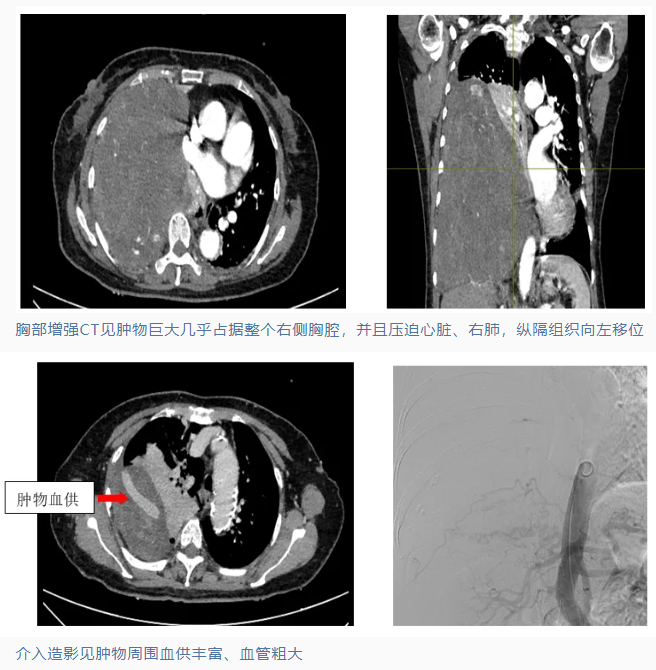

72岁的叶阿姨半年来饱受呼吸不畅、胸闷憋气、夜间无法平卧的痛苦,到院检查结果令人震惊——右侧胸腔内竟藏着一个比足球还大的肿物!25×22厘米的巨大肿瘤几乎填满整个右胸腔,将心脏和气管挤压到左侧严重变形。

"如果肿瘤继续生长,患者随时可能出现呼吸、心跳骤停的危险。"胸外科钟海辉主任指出,这个庞大的肿瘤与胸壁、纵隔、肺组织分界不清,紧密粘连,血供异常丰富,稍有不慎就会引发大出血,手术及麻醉的难度极高。更棘手的是,穿刺活检确诊为具有恶变倾向的孤立性纤维瘤,手术的关键是既要完整切除病灶,又需最大限度保留肺功能,这对手术团队提出了极高要求。

面对这颗随时可能引爆的"炸弹",为了制定更安全、高效的治疗方案,胸外科钟海辉主任联合介入科曾国斌主任医师、ICU黄寿新主任医师、心脏血管外科刘治元主任医师、麻醉科邓靖单主任医师、外科手术中心、输血科等团队开展多学科联合会诊(MDT),决定先由介入科团队率先出击,开展动脉造影+肿瘤血管介入栓塞手术,减少肿物周围血供,降低外科手术出血风险。